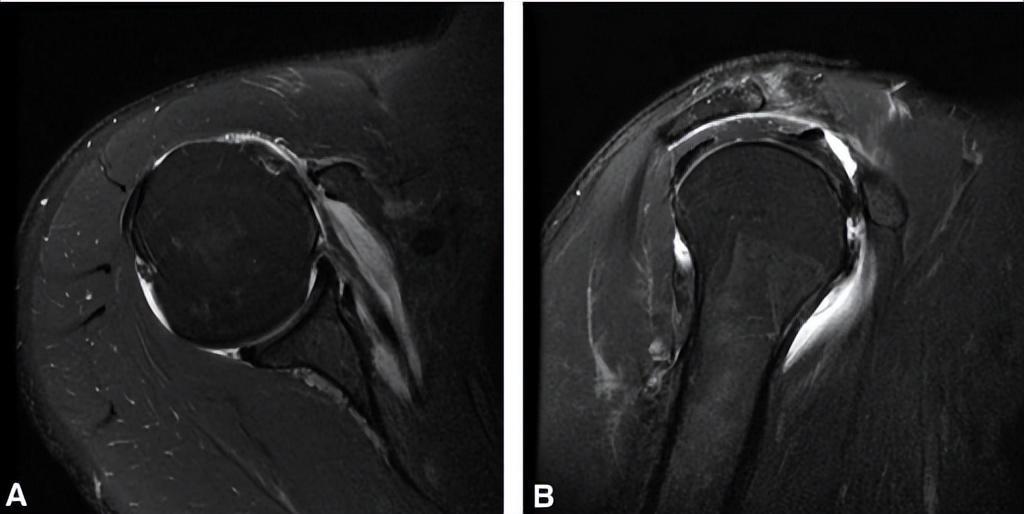

④MRI检测:MRI由于能够清晰的显示骨组织及软组织,以及软组织的炎症状态,已经成为肩关节最重要的检查手段(图3)。

图3 轴向(a)和矢状位(b)MRI能够显示狭窄的喙肱间距及肩胛下肌腱损伤以及局部炎症。